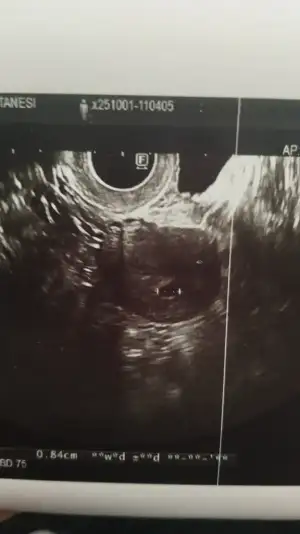

Betamı bilmiyorum kan bakılmamıstı ama kesem 9 mmdi bende de yolksac görülmedi sizim kese kaç mm cıktıEvet gittim kese boyu yeri şekli gayet güzel ama yolk sac gözükmedi benimde 5+5de sizin gittignde beta hcgnz kaçtı

O anki stresten sormayı unuttum Çarşamba 8.4mm di ama ekranı gösterdi bariz bir büyüme vardı kaç mm bilmiyorumBetamı bilmiyorum kan bakılmamıstı ama kesem 9 mmdi bende de yolksac görülmedi sizim kese kaç mm cıktı

Off umarom ikimizde güzel haberler alırız bende dün gittim 5+3 kesem 9.6 mm olmus ama hala yolksac yoktu domtor daha erken endişeye gerek yok dedi ama bilmiyorumO anki stresten sormayı unuttum Çarşamba 8.4mm di ama ekranı gösterdi bariz bir büyüme vardı kaç mm bilmiyorum

İnşallah Ne güzel doktorunuz olumlu konuşmuş benim ki hiç olumlu değildi negatifi daha çok dillendirdi boş gebelik olabilir dediOff umarom ikimizde güzel haberler alırız bende dün gittim 5+3 kesem 9.6 mm olmus ama hala yolksac yoktu domtor daha erken endişeye gerek yok dedi ama bilmiyorum

Benim bundan önceki boş gebelikti o yüzden cok korkuyorum tekrar aynısı olacak diyeİnşallah Ne güzel doktorunuz olumlu konuşmuş benim ki hiç olumlu değildi negatifi daha çok dillendirdi boş gebelik olabilir dedi![]()

İnşallah bu carsmaba gününün ultrason kağıdı bu gününkini almayı unuttum ama buna göre bariz büyümüştüİnsallah dolar kesemizin ici ben pazartesi tekrar gidicem senin hic usg foton var mı atar mısın

Benimkimde dün böyleydiİnşallah bu carsmaba gününün ultrason kağıdı bu gününkini almayı unuttum ama buna göre bariz büyümüştü